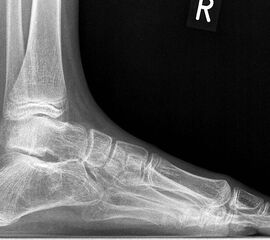

Diagnostisch sollte neben Röntgenübersichtsaufnahmen (indirekte radiologische Zeichen: Dorsaler Traktions-Osteophyt am Taluskopf, „talar beaking“; kontinuierliche Linie der Trochlea-tali-Kontur übergehend in die Sustentaculum-tali-Kontur, „C-Zeichen“ (Abb. 11) 10) immer die dreidimensionale Bildgebung eingesetzt werden. Das MRT (mit Kontrastmittel) kann die Struktur der Brückenbildung und z.B. die Qualität des Restgelenkes (Knorpel-Dicke) besonders gut abbilden; das Dünnschicht-CT zeigt die knöcherne Feinstruktur im Bereich der Coalitio und den oft sehr schrägen Spalt-Verlauf im Frontalschnitt dagegen häufig genauer. Meist findet sich die Überbrückung im Bereich der medialen Facette; die Schichten sollten jedoch bis weit nach dorsal beurteilt werden, da ansonsten dorsomediale Formen übersehen werden können. Rozansky et al 7 unterschieden fünf morphologische Typen auf der Basis von 3-D-CT-Rekonstruktionen. Allerdings ist eine prognostische Zuordnung bisher nicht möglich.